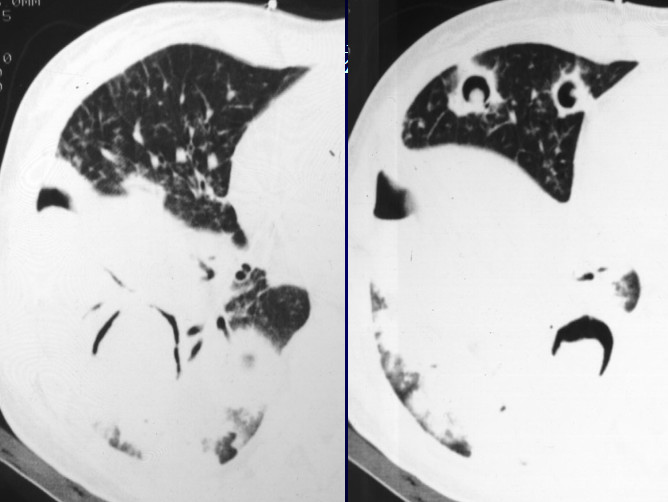

X线胸片表现为在两侧中上肺有斑片状阴影,隐约可以看到小的空洞样病变。CT显示的很清楚,可以看两肺尖空洞,周围有小的点状播散病灶。在上叶前段、左上叶尖后段也有空洞,这些空洞的周围可以看到树芽征,小叶中心的病变。所以这是典型的以中上肺分布的伴支气管播散病灶,为典型的肺结核病变。